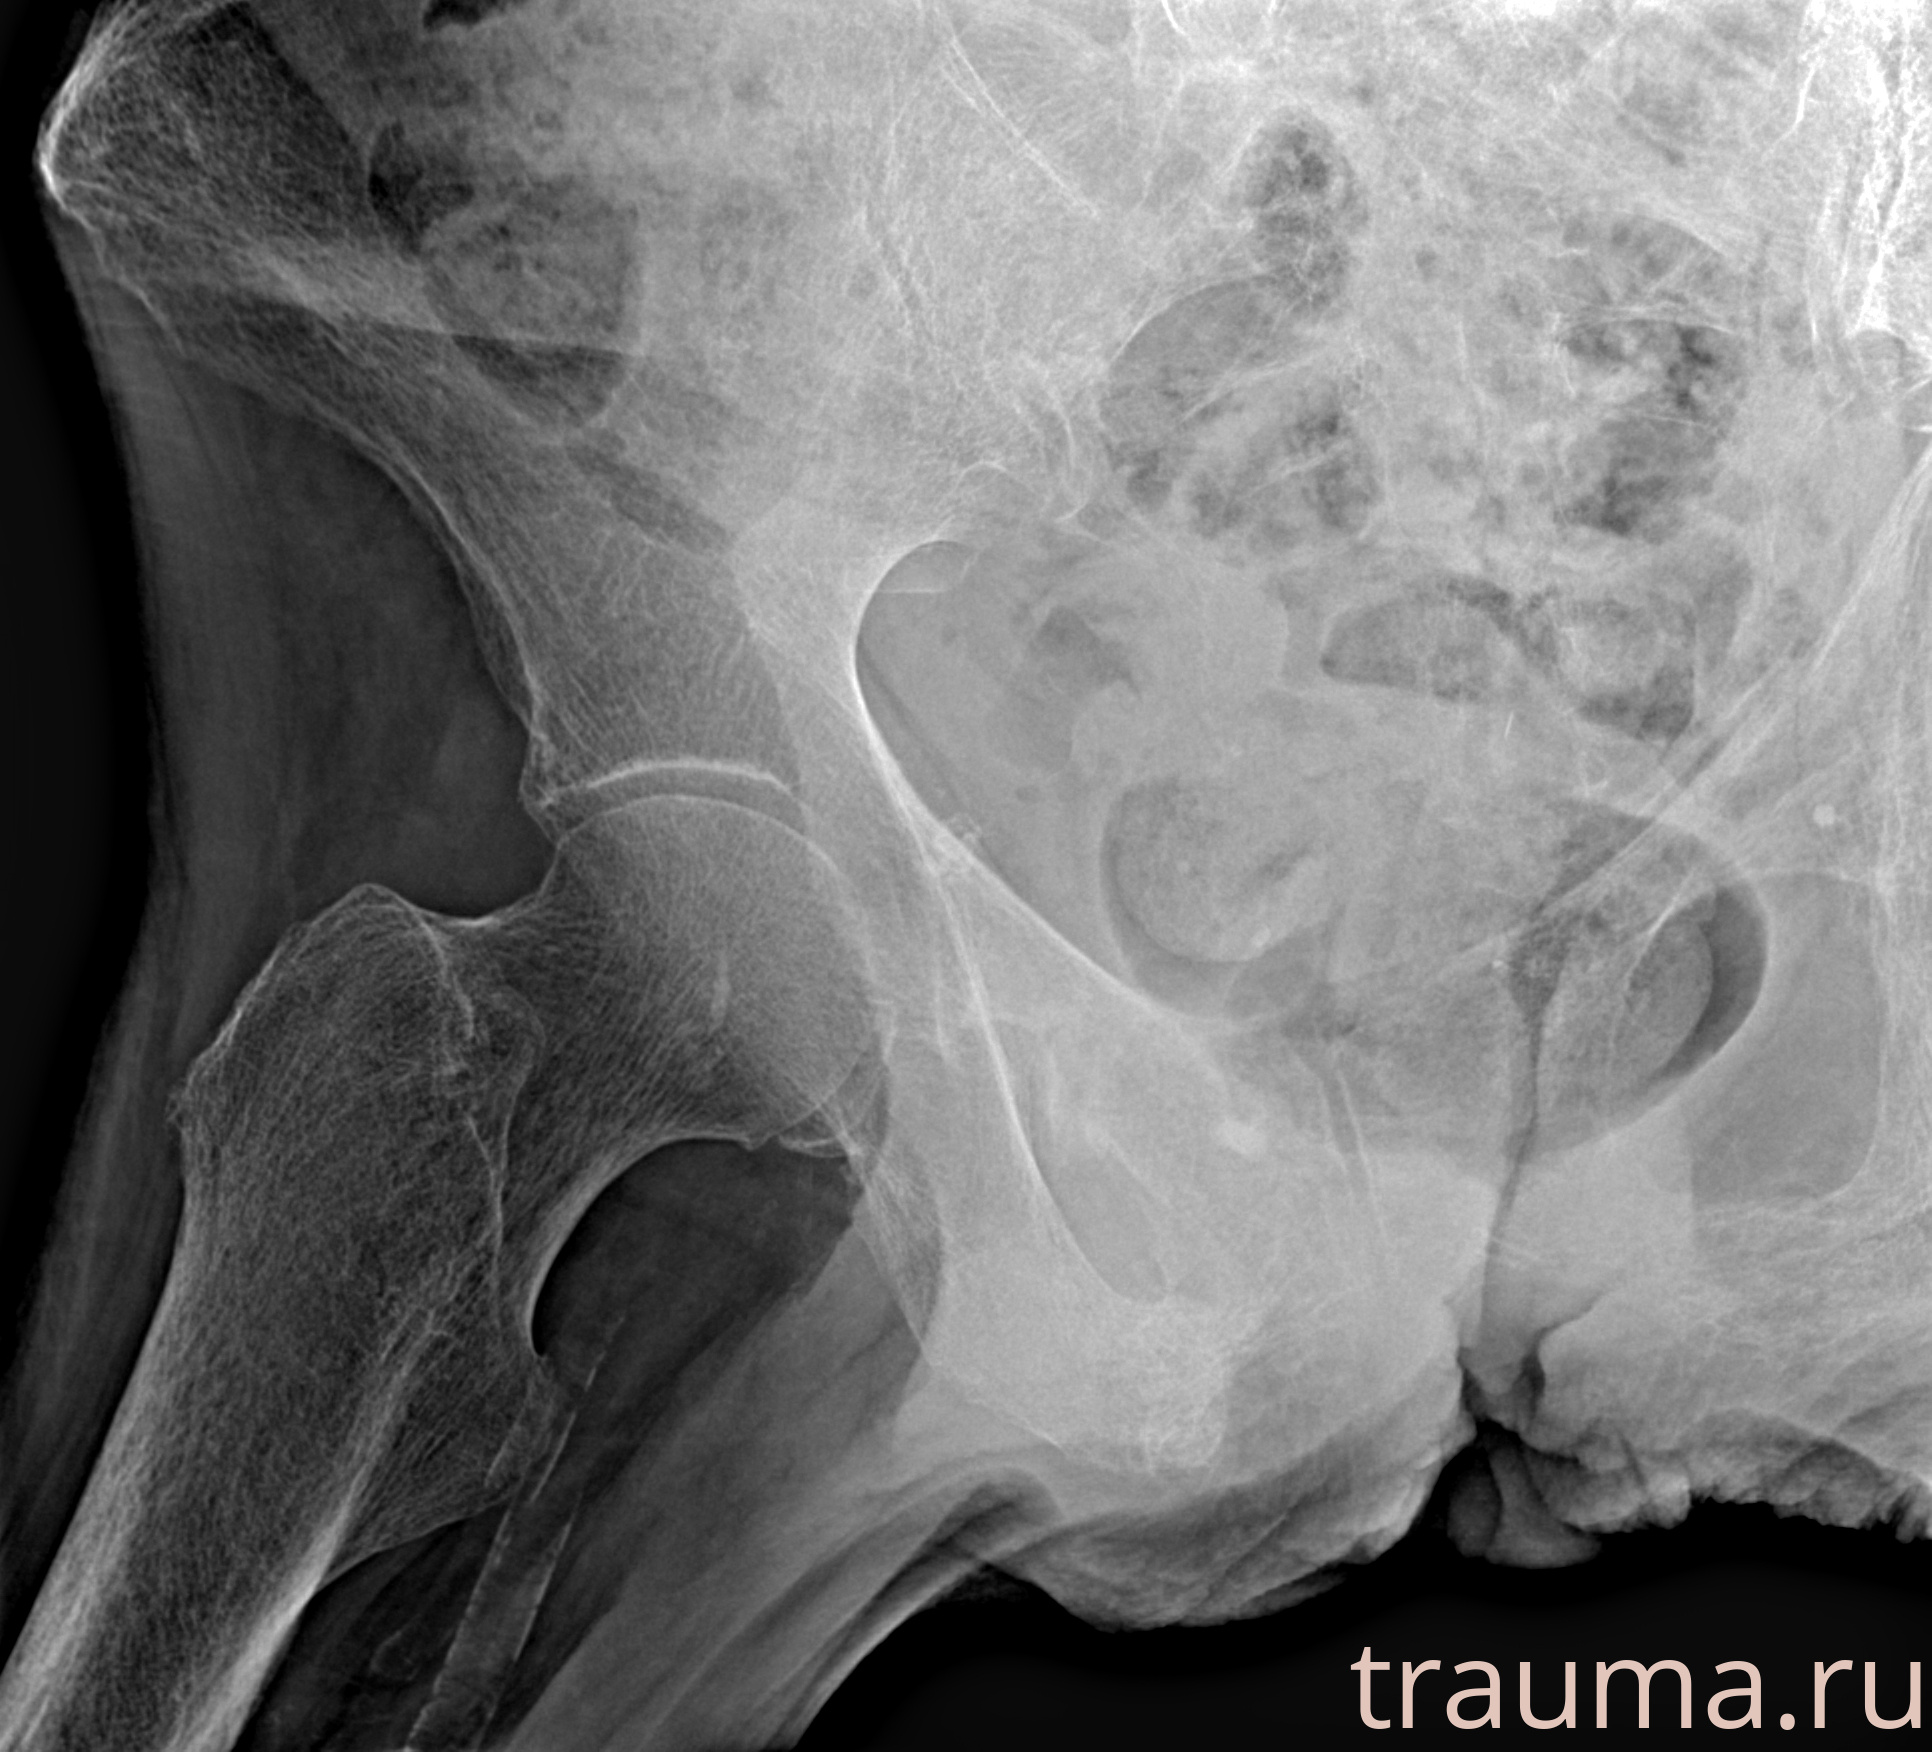

Рентген на дому: по вашему адресу приезжает врач-рентгенолог, травматолог-ортопед с мобильным рентгеновским аппаратом, проводит диагностику травмы или заболевания, делает необходимые рентгенограммы, дает рекомендации по дальнейшему лечению. Получить качественные снимки в домашних условиях возможно благодаря уникальной методике, разработанной МосРентген Центром для института  Склифосовского